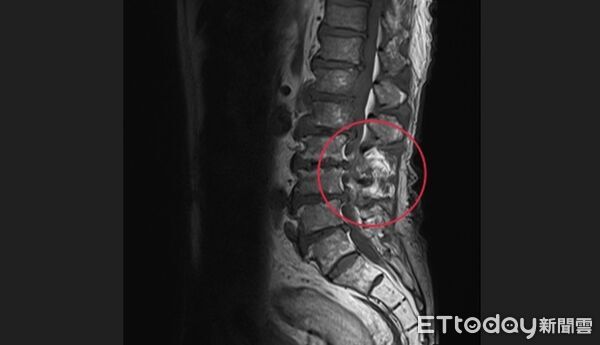

▲台中一名王姓女子下背痛到不支倒地,就醫檢查才揪出是鏈球菌感染惹禍。(圖/亞大附醫提供)

亞洲大學附屬醫院感染科主治醫師張為碩表示,患者年初開始出現下背痛後,讓她整天鬱鬱寡歡,甚至連出門都興致缺缺,每天口頭禪就是「我快痛到快趴在地上了」,掛過急診吃止痛藥,但始終沒有明顯改善,後來患者疼痛症狀加劇,改掛感染科,醫師懷疑可能是「脊椎骨髓炎」引起,隨即安排患者住院及接受電腦斷層與核磁共振檢查,隨即確診是腰椎第二、三節骨髓炎,後續血液培養結果也發現鏈球菌指數偏高,原來是「細菌跑到骨頭裡面了」。